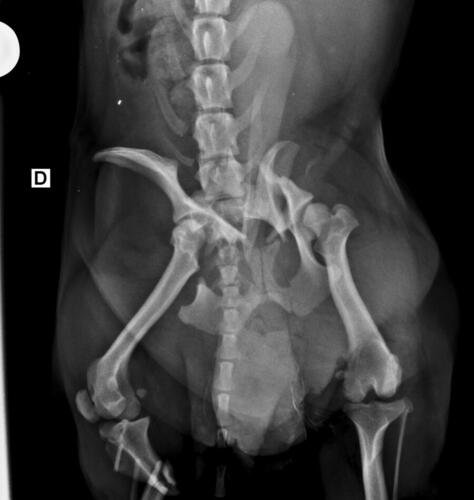

Olá, me chamo Jacqueline sou a mãe do chokito de 4 patas 🐶. No dia 07/02/2025 chokito foi atropelado em frente a minha casa, onde resultou no quadril dele quebrado e a patinha direita traseira quebrada tbm (a tíbia). Quem atropelou ele não parou pra prestar socorro a ele, e mto menos quis saber oque havia acontecido. Chokito foi atropelado na frente dos meus filhos, duas crianças um autista de 5 anos e uma criança de 3 anos, onde o acidente poderia ter acontecido com um deles, mas graças a Deus, Deus livrou eles, mas infelizmente o chokito não. Desde o dia 07 o chokito sofre de fortes dores constantes, onde ele não consegue se movimentar, para se alimentar ele precisa de ajuda, pra beber água, está com dificuldade em evacuar por conta das fortes dores que ele vem sentindo. Preciso de ajuda pra dar uma qualidade de vida pro chokito voltar a andar e parar de sentir dores constantes. A cirurgia ficou em torno de R$5,500 reais, um valor ao qual eu não consigo pagar, tudo tem sido mto caro, tenho gastado com remédios, Raio x, veterinário, já a cirurgia está mto a cima do que eu poderia pagar pra ajudar ele. Chokito é um cachorro que já foi abandonado e maltratado, pegamos amor e cuidamos dele, meus filhos sofrem por não poder brincar com o cachorro deles e ver o cachorro sempre gritando de dor é uma tristeza para todos nós. Por isso preciso de ajuda pra custear essa cirurgia que ele tanto precisa. Por favor quem puder me ajudar de alguma forma pra que ele volte a andar e parar de sofrer. Estou com meu coração dilacerado vendo ele sofrer sem poder fazer mais do que eu já estou fazendo que é cuidar dele. Cada dia que passa é mais tempo que ele passa sofrendo e agravando a situação que ele se encontra.